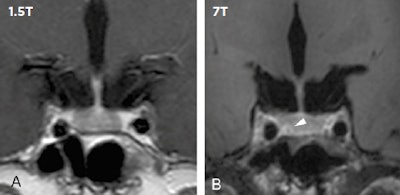

The possibility of 7-tesla revealing increased anatomical detail and achieving better contrast-to-noise ratio (CNR) of brain structures and brain pathology can help to increase the confidence in several diagnoses, including microinfarcts, pituitary microadenomas, and cortical dysplasia in epilepsy patients, according to the technique's supporters.

"At the end of the day, the CNR of 7-tesla is more important than the increased signal-to-noise ratio (SNR), compared to 3-tesla and 1.5-tesla MRI. This means that 7-tesla can better detect pathologies, including small lesions," noted Dr. Jeroen Hendrikse, chair of the radiology department at the University Medical Center (UMC) in Utrecht, the Netherlands. "Furthermore, methods to improve CNR at 7-tesla can also be exploited for better diagnosis at 3 tesla and 1.5 tesla, as has been shown for the detection of cortical microinfarcts."

Specifically, he discussed at ECR 2019 how recent work shows that 7-tesla detects small pituitary adenomas in patients with Cushing's syndrome when no pituitary lesion was detected at lower MRI field strengths. Furthermore, 7-tesla vessel wall imaging can depict the burden of intracranial atherosclerosis, including small intracranial plaques. However, he sounded a note of caution.